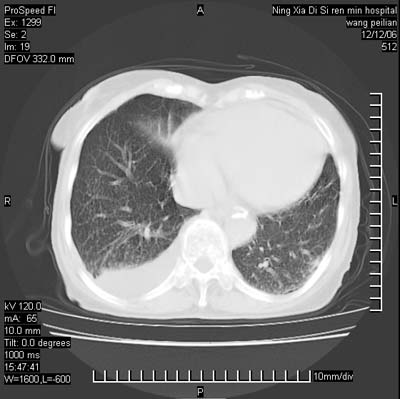

标题: CT5609:胸部:女77 病史不详

两肺可见多个大小不等的结节,左侧有胸水,纵隔淋巴结增大,考虑是细支气管肺泡癌

两肺尖纤维索状影,两下肺结节块状影,且有钙化灶,右胸腔积液。考虑肺结核并胸膜炎。

两肺尖纤维索状影,两下肺结节块状影,且有钙化灶,右胸腔积液。考虑肺结核并胸膜炎肺间质纤维化

考虑:1、慢性支气管炎合并全小叶型肺气肿、间质纤维化;

2、双肺结核;

3、右侧胸膜炎(积液)。

1、双肺继发型肺结核(以纤维、增殖灶为主);

2、右侧胸腔积液;

3、其余符合老年肺改变。

双肺见多个结节状及条索状影,双侧胸腔积液,右侧叶间积液,考虑结核性胸膜炎